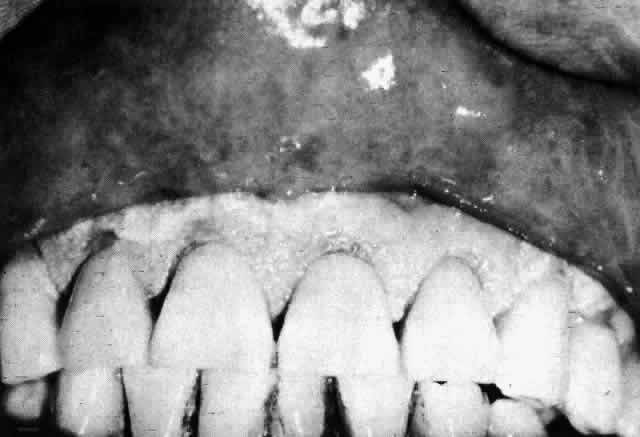

CICATRICIAL PEMPHIGOID

Cicatricial pemphigoid (benign mucous membrane pemphigoid, ocular pemphigoid) is a chronic bullous dermatosis affecting primarily the mucous membranes (Fig. 11). A related bullous dermatosis in which skin lesions rather than mucous membrane lesions predominate is known as bullous pemphigoid. The two diseases have similar histopathologic features and are considered by some observers to represent opposite ends of a single spectrum of disease. In tracing the history of these diseases, one finds that as early as 1794 Wichmann42 reported a case of chronic bullous disease in which the eye was affected and that in 1858 Cooper43 described a patient with blisters of the skin and conjunctiva. Von Graefe44 associated essential shrinkage of the conjunctiva with the end stage of pemphigus, and it was not until 1911 that Thost45 distinguished “cicatricial pemphigoid” from the various forms of pemphigus, a separation that was later emphasized by Civatte46 and Lever47 on the basis of histopathologic studies.

Fig. 11. Cicatricial pemphigoid. Bullous lesions of the oral mucosa. (Courtesy of Dr. HB Ostler)

Cicatricial pemphigoid is often a severe, debilitating, blinding disease. Characterized by symblepharon, obliteration of the fornices (Fig. 12), and corneal ulceration and vascularization, it is one of the most difficult ophthalmologic problems to manage successfully. Severe lid distortion and a dry-eye syndrome may ultimately develop.